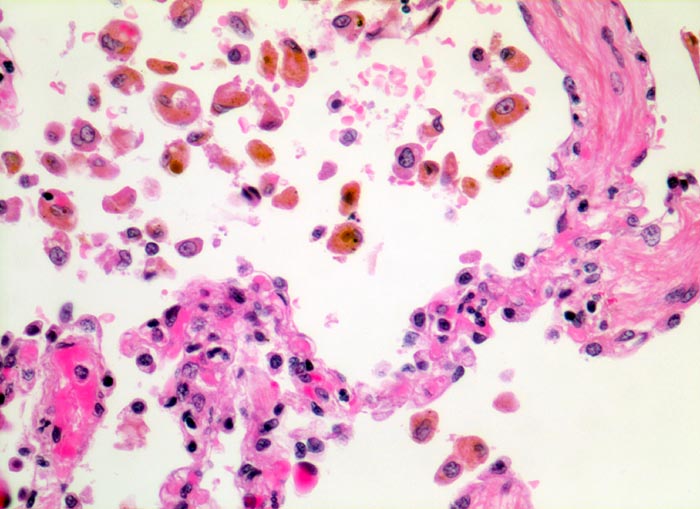

chronische Lungenstauung: Herzfehlerzellen

Die Alveolarsepten sind deutlich fibrotisch verdickt. Gleichzeitig ist die Gefässausstattung vermindert. Die aus den Kapillaren in die Alveolarräume ausgetretenen Erythrozyten werden von Alveolarmakrophagen phagozytiert. Die Makrophagen enthalten teils intakte Erythrozyten, teils braunes Hämosiderinpigment aus bereits abgebauten Erythrozyten.

Patient mit Mitralinsuffizienz.